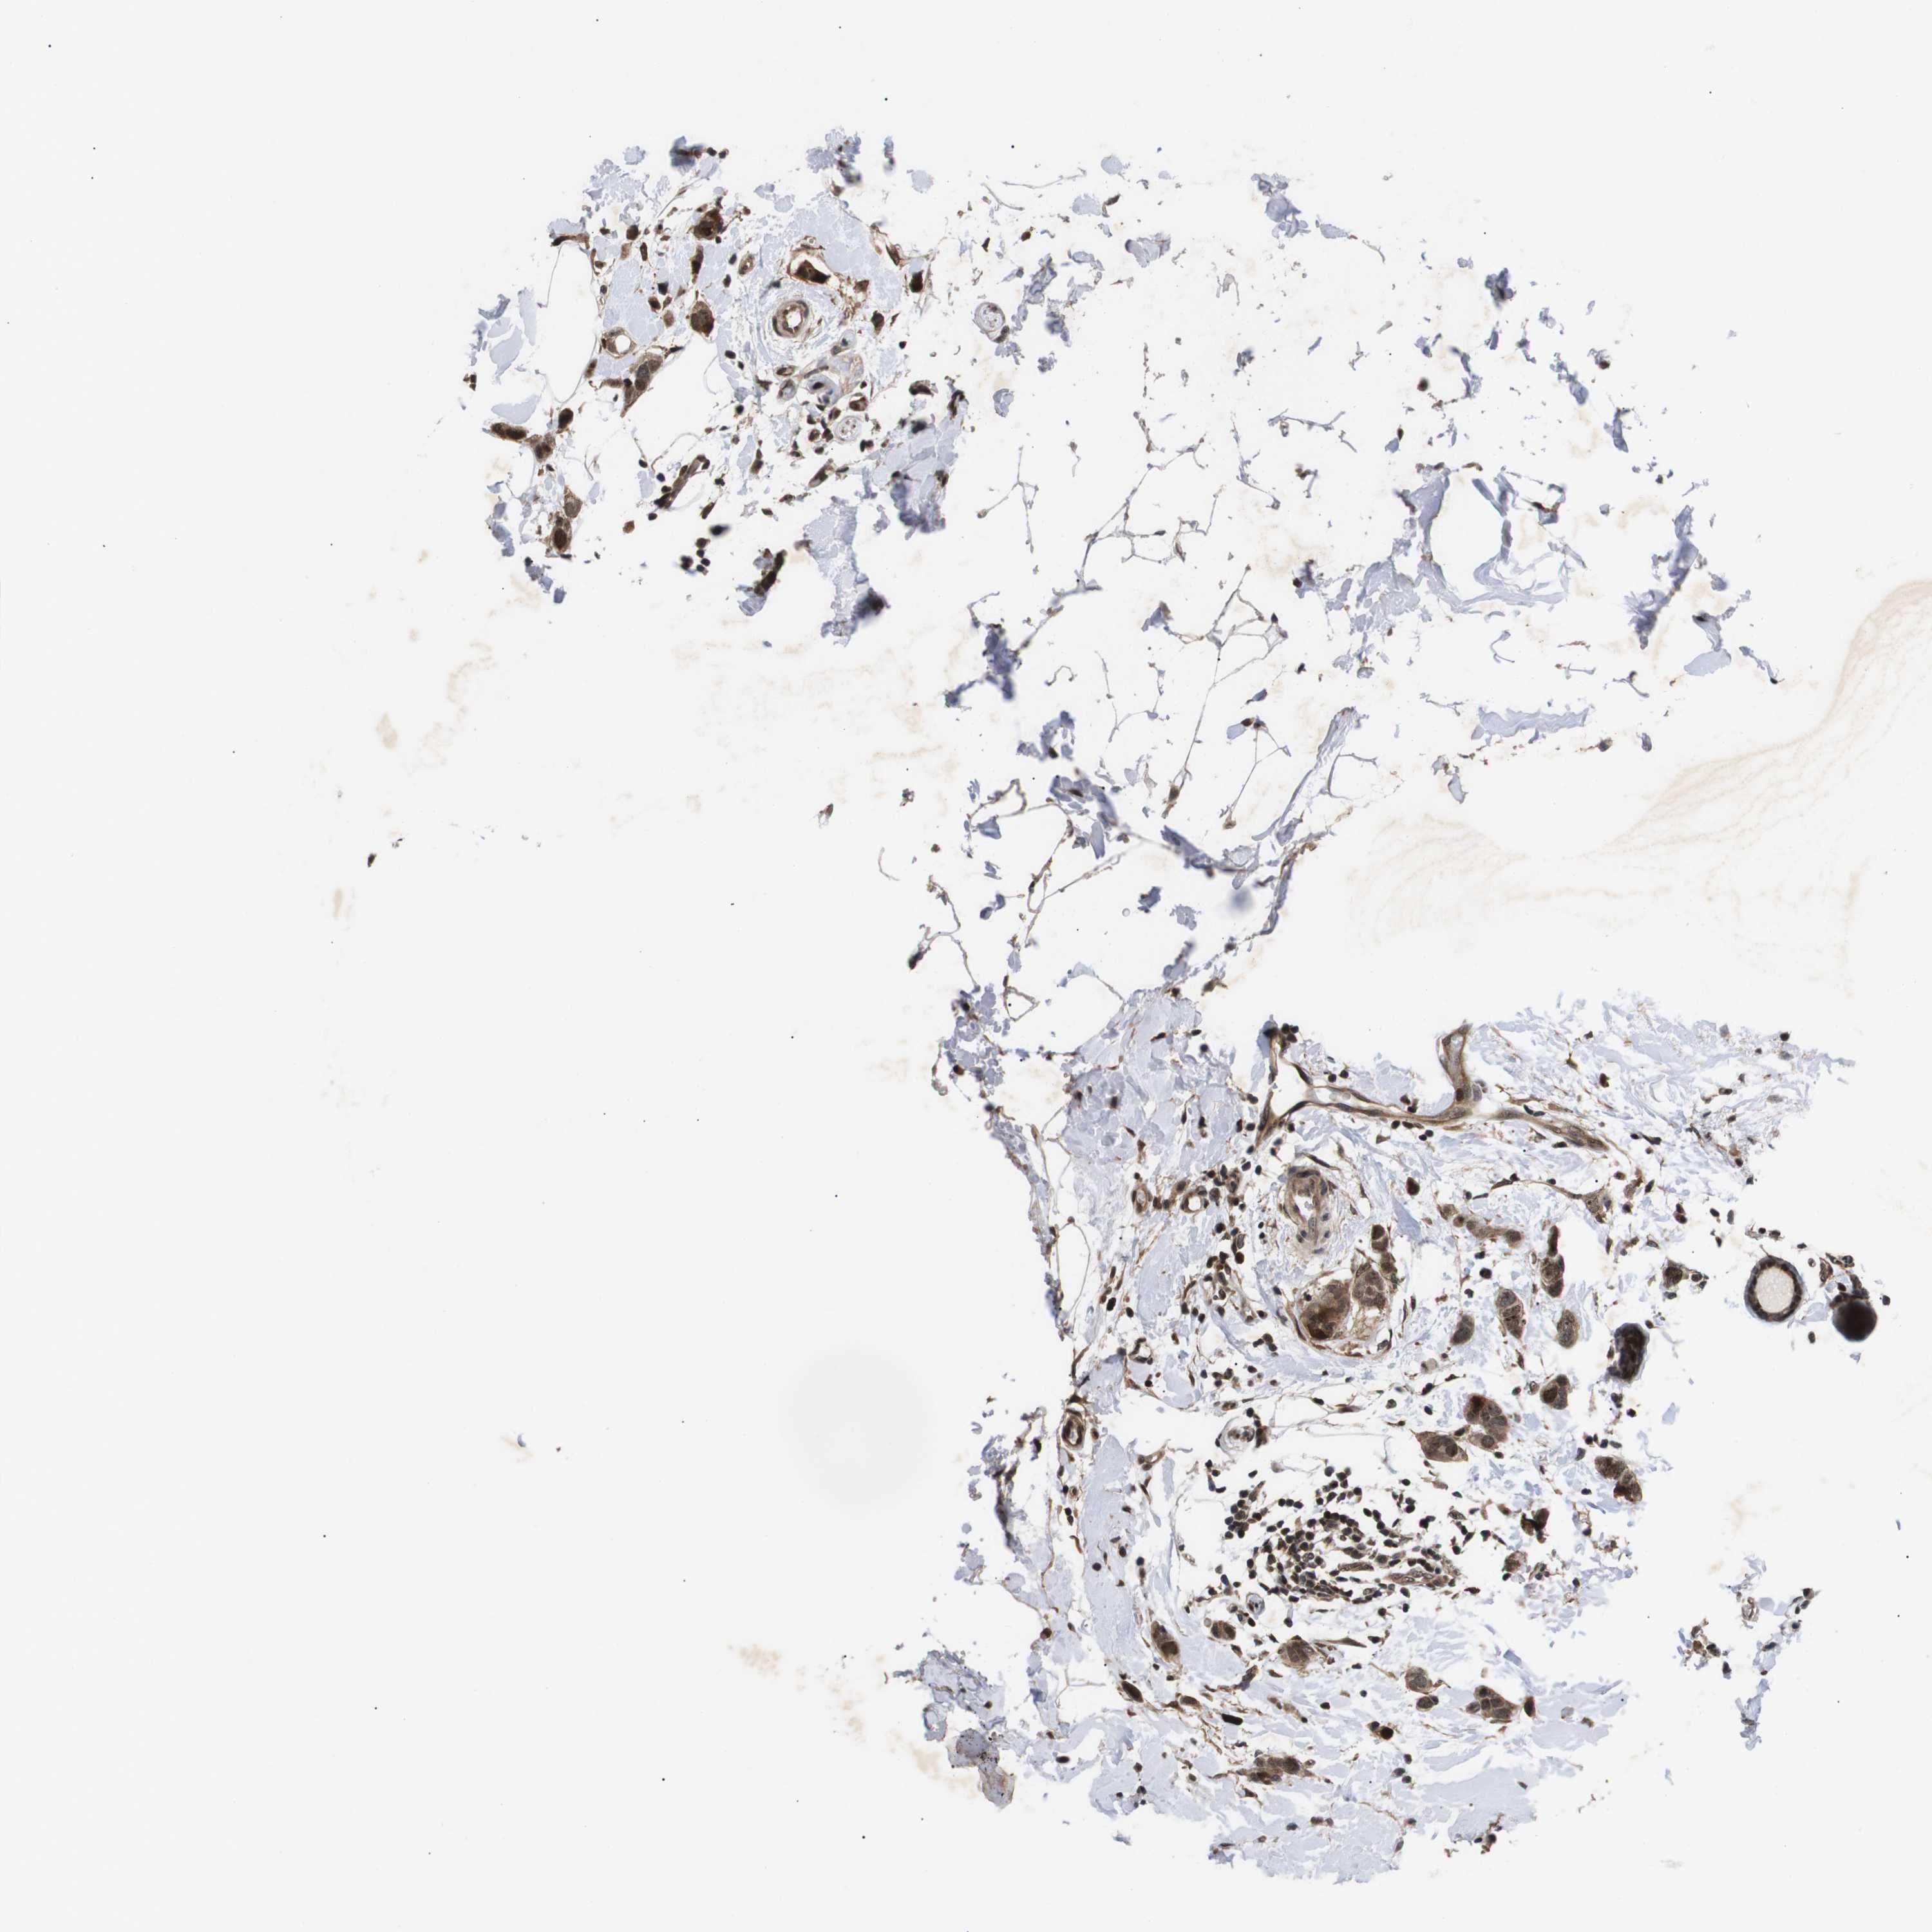

BRCA TCGA BRCA VALIDATION PROTEIN EXPRESSION

ANTIBODIES

AND

VALIDATION